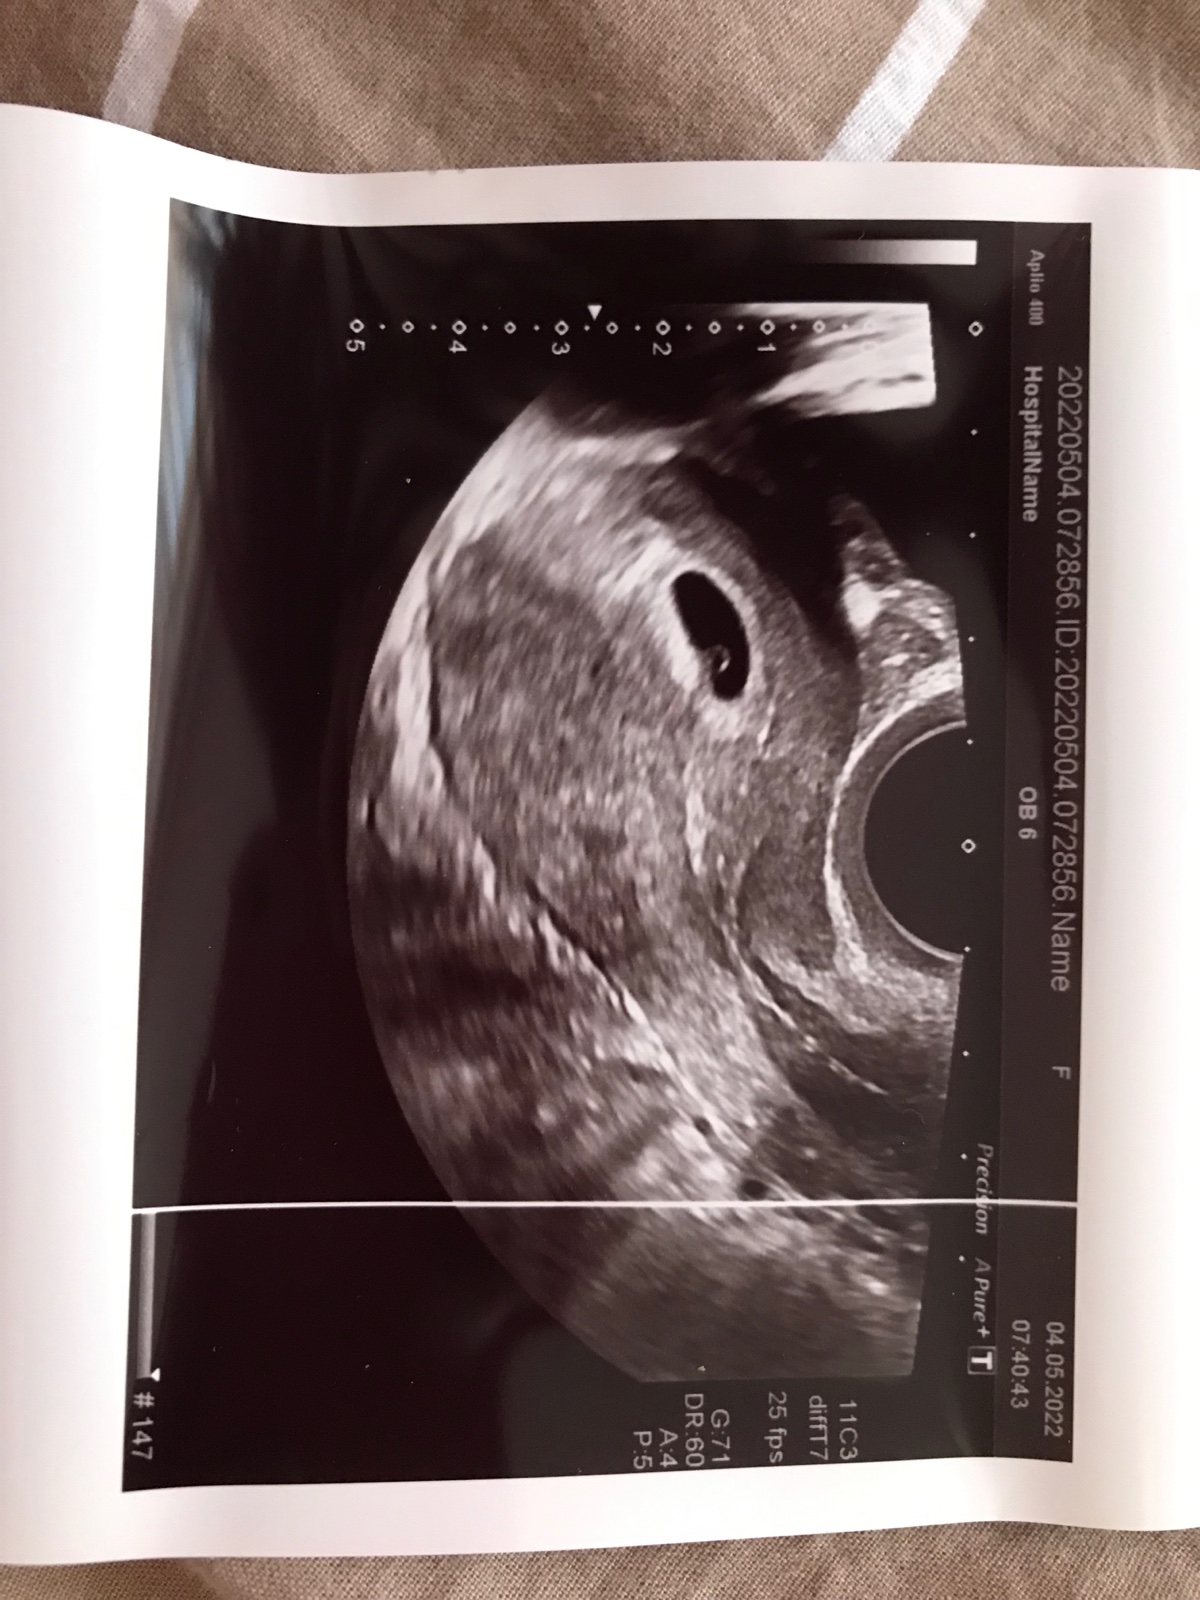

Ja som dnes bola u dr, podľa mojich výpočtov som ešte len na začiatku 5tt ,ale podľa ms by to už mal byť začiatok 8tt,tak ma chcel dr vidieť. Bol už vidieť malinký váčok odpovedajúci 5tt a mám ďalšiu kontrolu o týždeň v utorok a potom asi o dva týždne na potvrdenie ❤️.